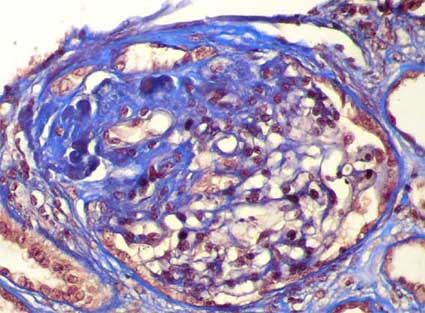

This category excludes all the other variants. It is defined by at least 1 glomerulus with collapse and overlying podocyte hypertrophy and hyperplasia.

The capillary walls present retraction and collapse. The lesion may be segmental or global and may involve peripheral or perihilar segments. The number of affected glomeruli is very variable. Adhesions to the Bowman’s capsule and hyaline lesions are unusual. There may be other lesions in some glomeruli: sclerosis, hypercellularity, tip lesion or global sclerosis.

Figure 12. See the glomerular tuft collapse, without conserved capillary lumina, with an irregular aspect and wrinkling of the capillary walls and with marked hypertrophy and hyperplasia of podocytes. This case corresponds to a 37-years-old male patient with NS, HIV negative, and without other predisponent factors: primary collapsing FSGS (idiopathic). (Methenamine-silver, X400).

Figure 13. Collapsing lesions can not be global and involve only some segments of the tuft. Although in this case the lesion is global, see greater collapse and podocyte hypertrophy and hyperplasia in the segments indicated with arrows (Silver, X.400).